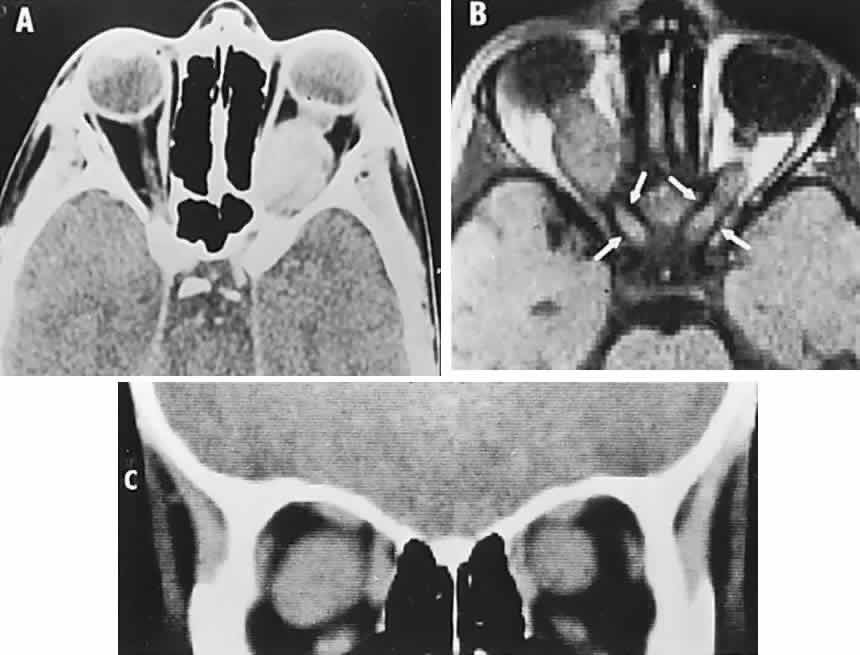

Microangiopathy of the brain, retina, and inner ear (Susac's syndrome) is a rare disorder predominantly affecting women of child-bearing age, but without a specific origin or systemic manifestations. An immune or coagulopathic background is unproved. Patients present with the following: vision loss due to branch retinal arteriolar occlusions with vessel hyperfluorescence on fluorescein angiography, and delayed leakage; hearing loss; multiple CNS infarctions.113 Efficacy of treatment with corticosteroids and immunosuppressive agents is uncertain, but hyperbaric oxygenation has been beneficial in a single case, with rapid visual improvement.114